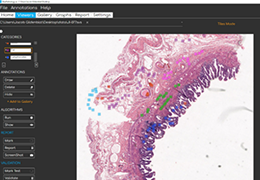

ART-Plan™ Artificial Intelligence Contouring